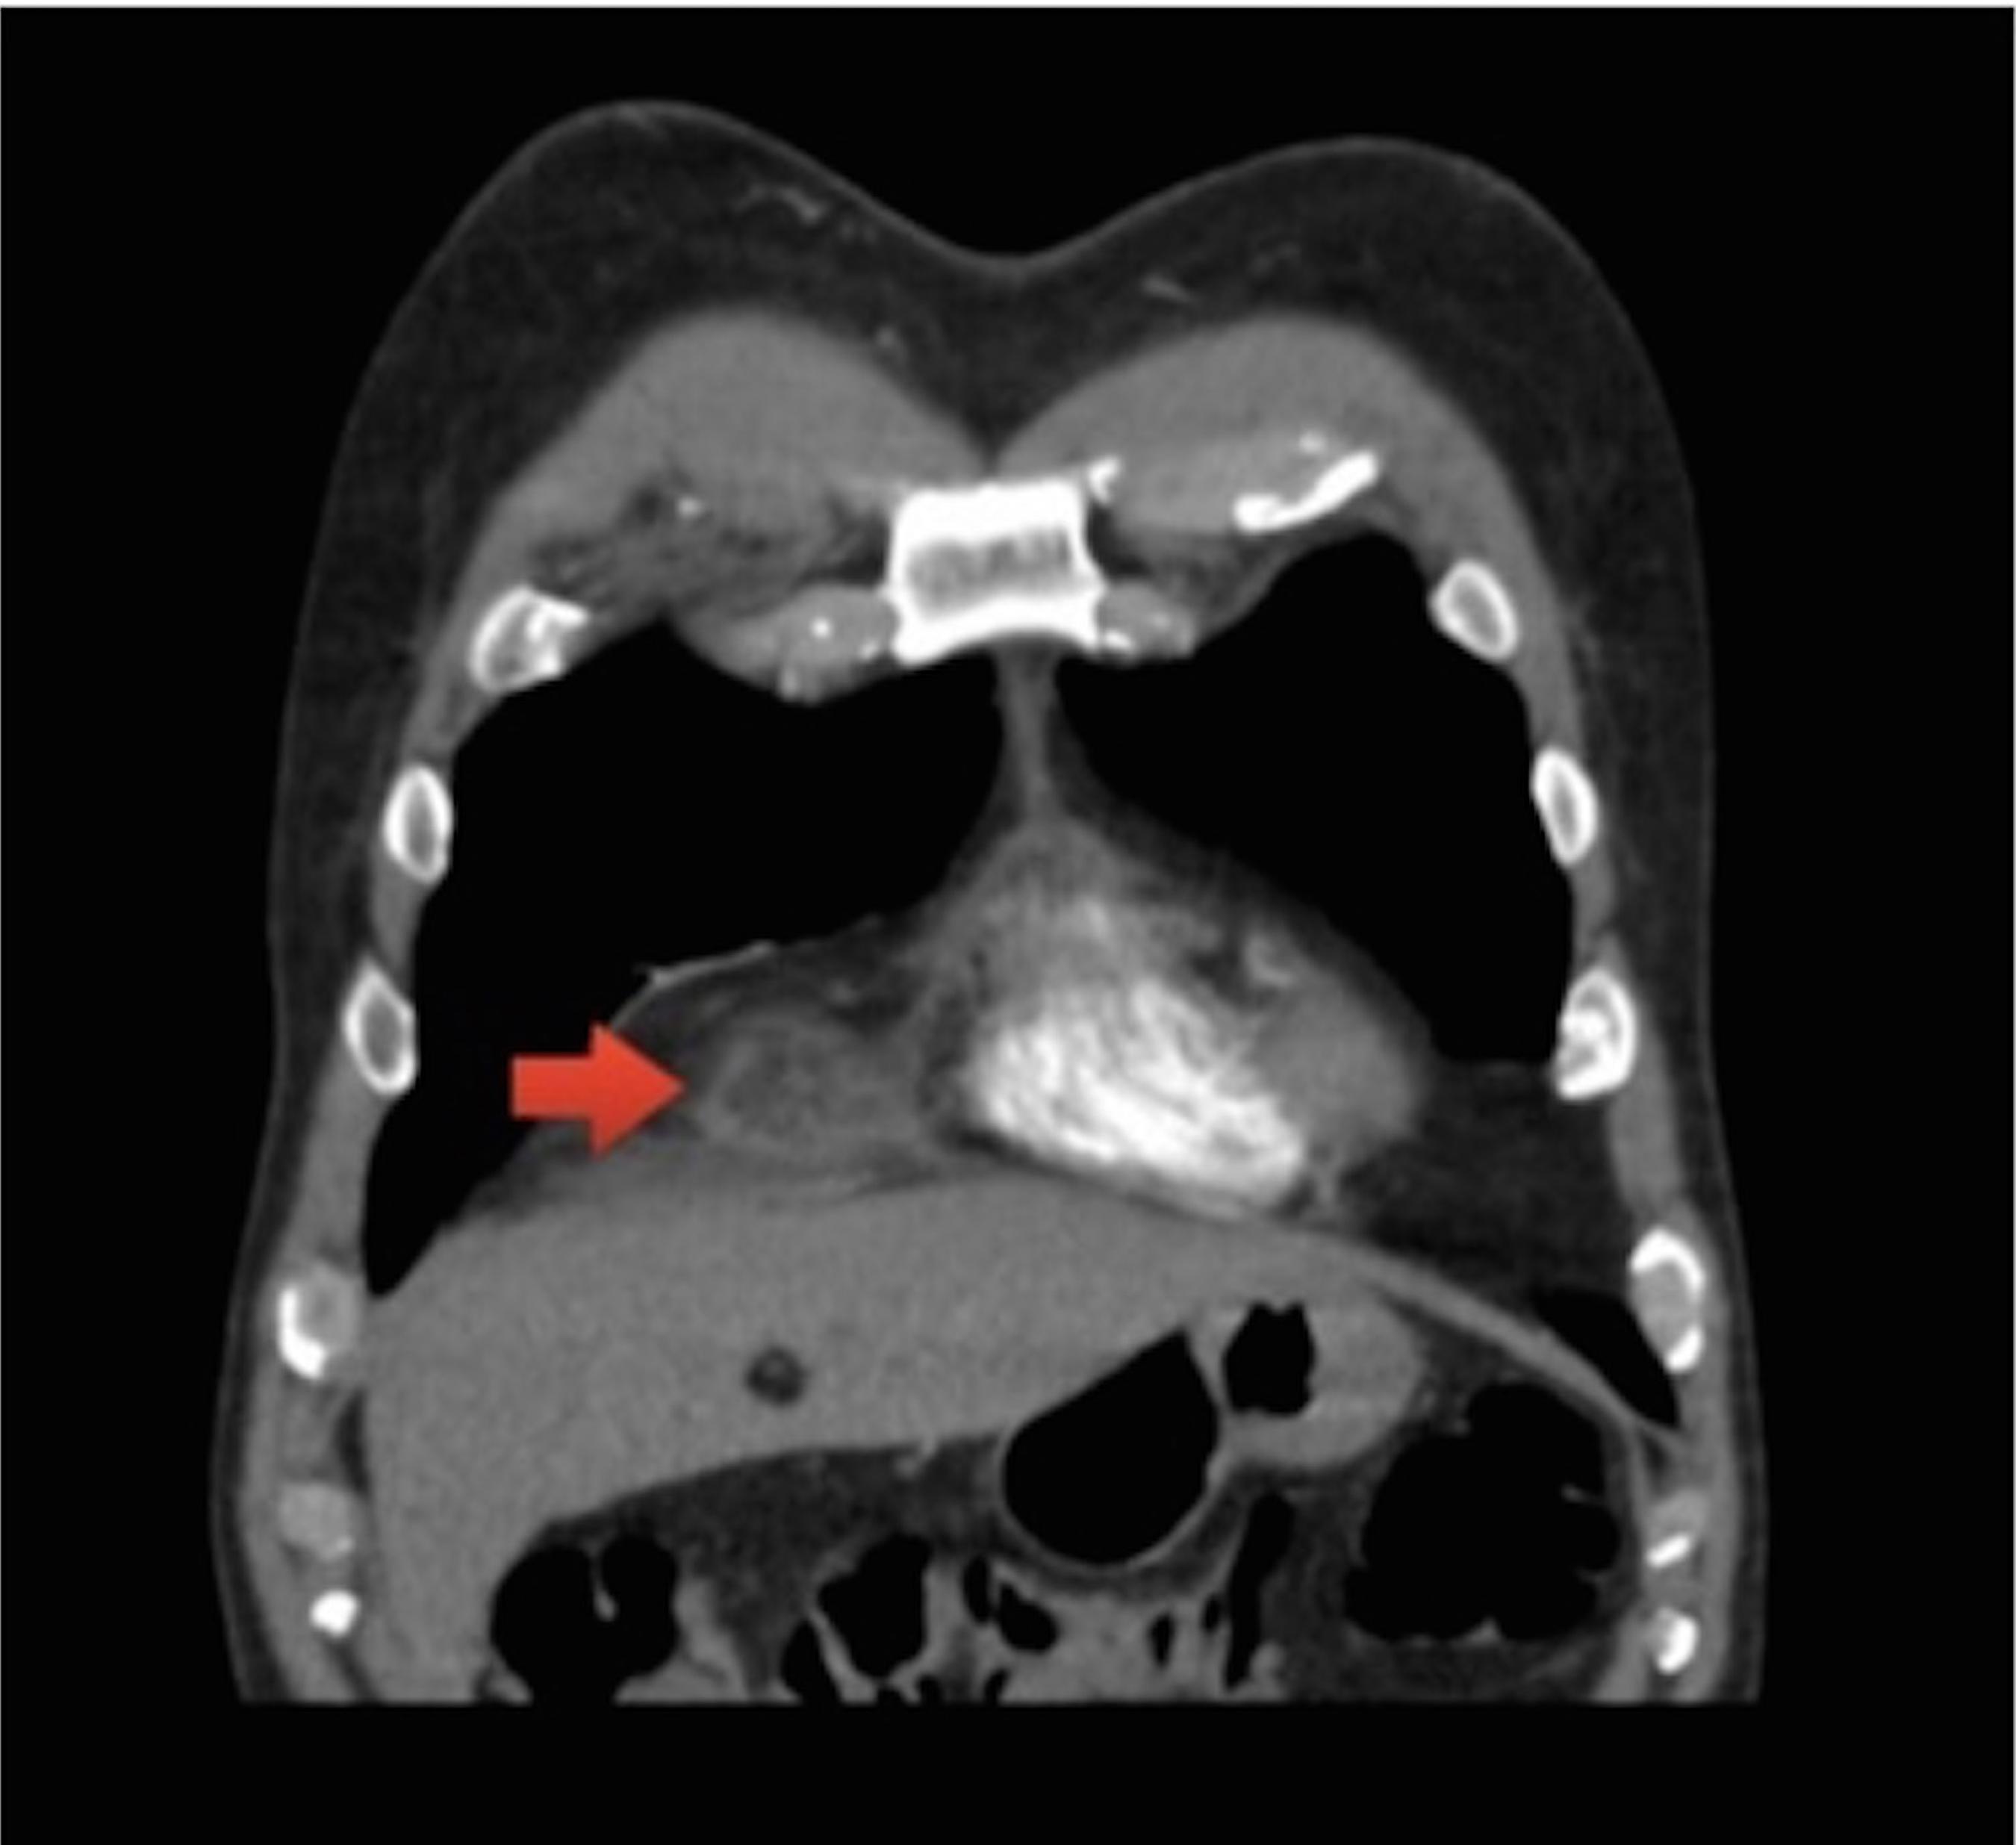

Necrose da Gordura Epipericárdica. Um Importante Diagnóstico Diferencial na Dor Torácica Sanar

Necrose da Gordura Epipericárdica. Um Importante